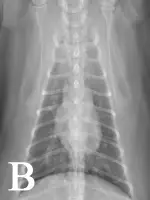

FIGURE 1

Bronchointerstitial pattern in the caudal lung fields (A and B). Enlargement of the caudal pulmonary arteries is evident on the ventrodorsal (B) projection.

In symptomatic cats, a positive antigen test is considered diagnostic of a mature infection but a negative result is ambiguous. Cats have few adult worms, so the amount of circulating antigen may fall below the detection limit. Male-only infections can also lead to false-negative results. The presence of antibodies indicates exposure to heartworm but does not necessarily denote an adult infection. Conducting both antibody and antigen testing increases sensitivity of detection as compared with conducting either test alone.1 Radiographic lesions (eg, hyperinflation, varying patterns of parenchymal infiltrates, enlarged caudal pulmonary arteries) help support a diagnosis of heartworm but are nonspecific and can resolve within a few months of infection in cats.5,6 Echocardiography provides a definitive diagnosis if heartworms are observed.